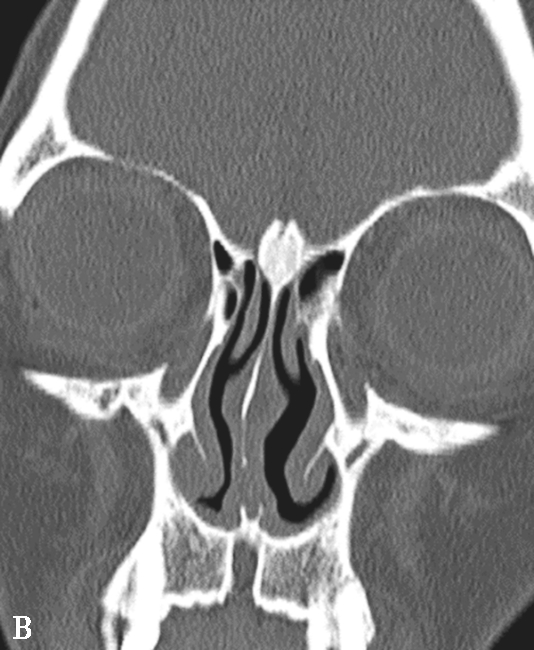

鼻窦过度气化、未发育或发育不良均以额窦最为常见,过度气化的额窦可伸展至颧突,向上至额结节水平以上,或超过眶顶至视神经孔(图1-3-9A),未发育或发育不良的额窦表现为额窦间隔缺如,只有单侧一个额窦窦腔,或双侧额窦窦腔均发育不良(图1-3-9B)。眶上筛房是额窦区域外侧的气房,亚洲人少见,冠状面上表现为随着扫描层面的后移,它的横径逐渐延长(图1-3-9C)。鼻中隔偏曲是指鼻中隔向一侧或两侧弯曲(图1-3-9D),或鼻中隔一侧或两侧局限性凸起,可引起鼻塞、鼻出血以及头痛。鸡冠可以发生气化,引流至额隐窝,如果开口闭塞,鸡冠内可产生黏膜囊肿(图1-3-9E)。

图1-3-9 其他常见解剖变异

A.额窦过度气化;B.额窦未发育;C.眶上筛房;D.鼻中隔偏曲,形成嵴;E.鸡冠气化并感染